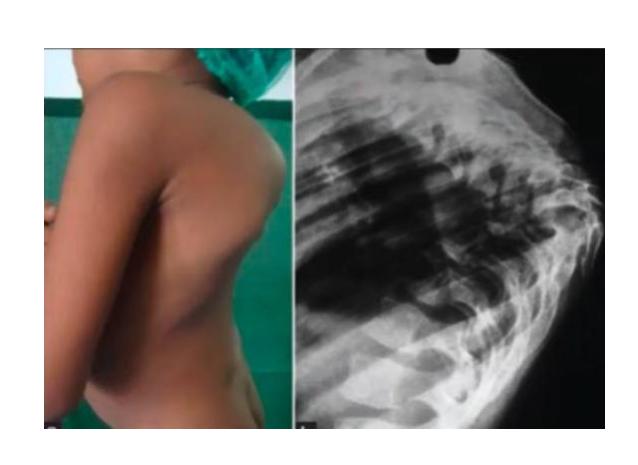

What is this deformity?

- Gibbus deformity

What is the deformity in this picture?

What is the most common cause?

- TB, congenital POTTS